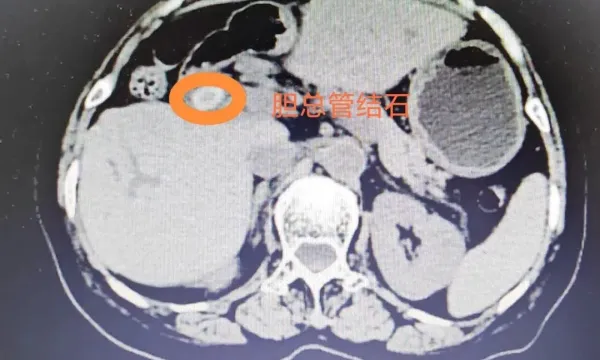

- 宝鸡市中心医院医学影像科:以精准影像护航健康,用优质服务温暖...

- 宝鸡市中心医院港务区院区:厚德精医守肝胆 暖心为民践初心

宝鸡市中心医院港务区院区:厚德精医守肝胆 暖心为民践初心